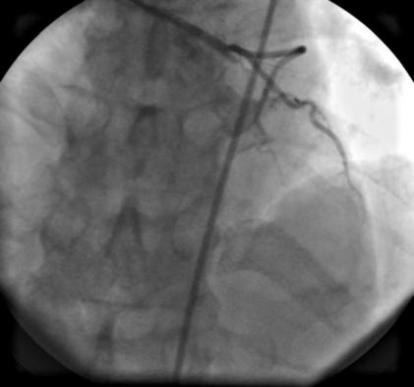

1、冠状动脉造影术、经皮冠状动脉成形术和支架植入术:能独立开展冠状动脉造影(CAG)术、经皮冠状动脉成形术(PTCA)和冠状动脉内支架植入术(STENT),确诊冠状动脉病变程度,治疗冠心病,心绞痛和心肌梗死。

2、急性心肌梗死急诊冠脉开通(PCI)术:急诊PCI术,抢救急性心肌梗死,对急性心肌梗死患者行急诊冠脉手术,开通闭塞血管会明显降低患者的死亡率。心内科已经开辟绿色通道,医护人员和介入手术室24小时待命,为患者服务。

3、冠状动脉慢性闭塞病变(CTO)的介入治疗技术:能显著改善心脏功能和预防心肌梗死后心功能不全、恶性心律失常的发生率。